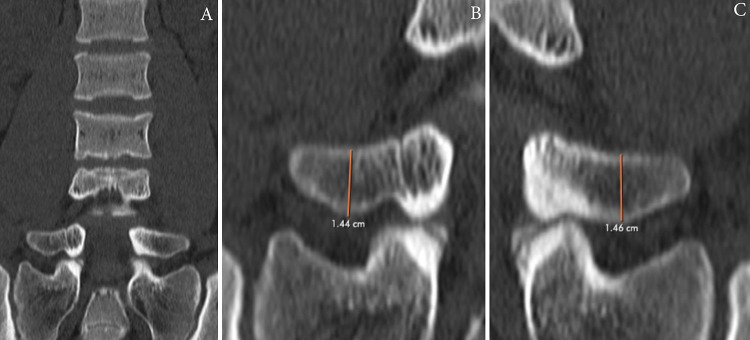

Observations: In this case, the Castellvi classification system failed to identify the patient (with 2 years of back and L5 pain) as having an LSTV, even though he displayed LSTV-like anatomy because both L5 transverse process heights measured less than 19 mm. He attained brief but significant relief from bilateral injections into the L5-S1 transverse/ala region and underwent a minimally invasive bilateral decompression of L5-S1 with almost complete relief of his symptoms maintained more than 6 months postoperatively.

Lessons: Given that the patient gained significant relief from treatment of transitional anatomy that failed to be identified using Castellvi's classification system, this case suggests that transverse process height may not be adequate or even the most clinically relevant indicator in identifying LSTV anatomy, which is a precursor to the diagnosis of Bertolotti's syndrome.